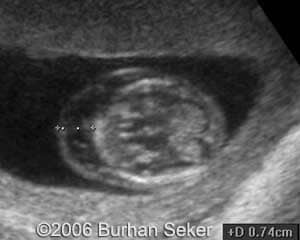

This a fetus with a cystic hygroma diagnosed at 13 weeks and 3 days. Karyotype was normal. The pregnancy was interrupted at 16 weeks.

At 13 weeks